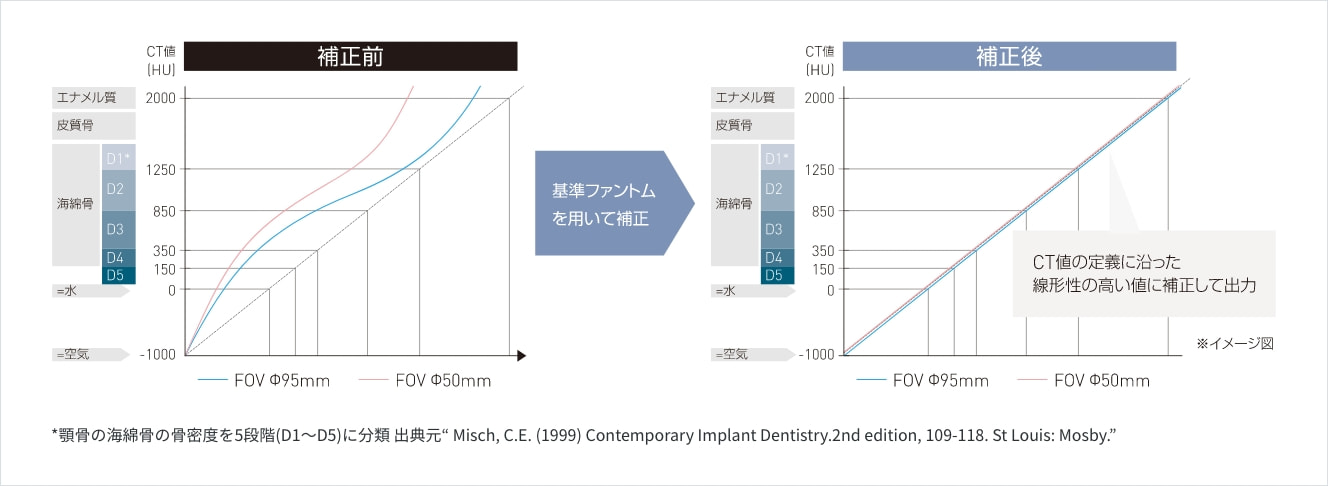

画素値を補正CT値として活かす

CT値が既知の基準ファントムを用いて補正を行います。CT画像で顎骨の形状や構造を見るだけでなく、任意領域のCT値を表示、またCT値を色付け表示することで顎骨の硬い・軟らかいを視覚的に確認することができます。